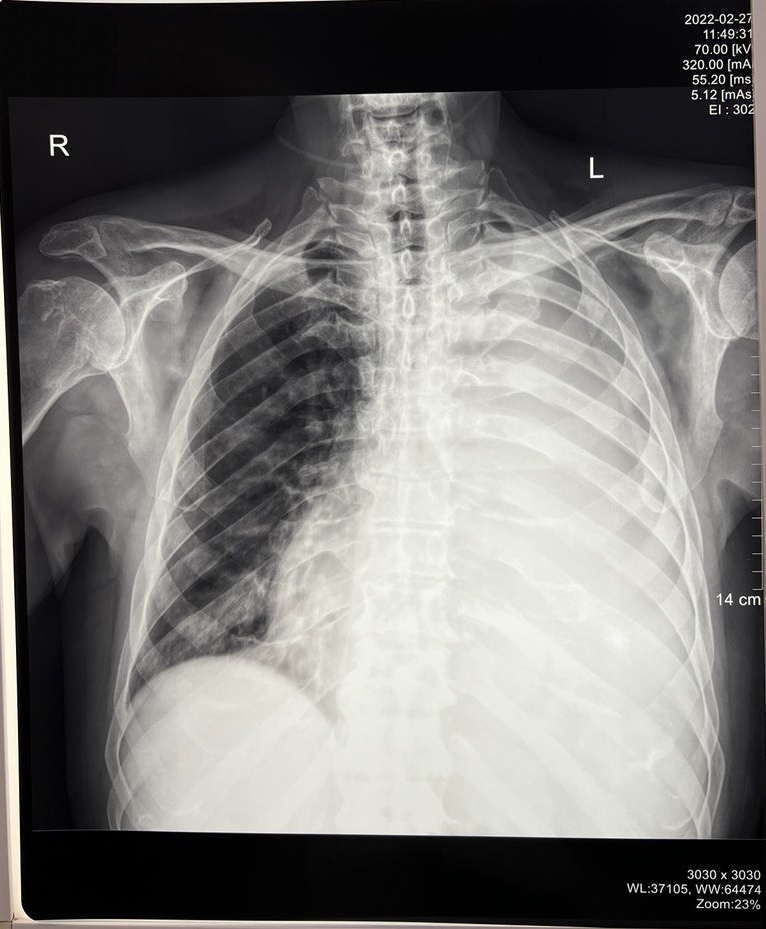

27 февраля 2022 г. была выполнена контрольная рентгенограмма, показавшая тотальный ателектаз левого легкого. Количество жидкости достоверно не было определено.